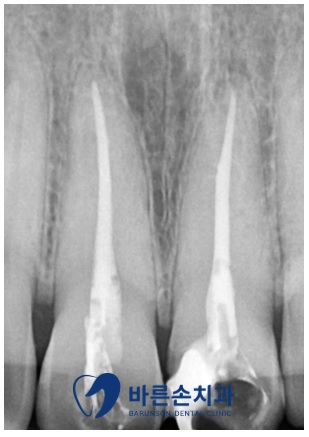

정확한 손상 정도를 확인 하기 위해 엑스레이 촬영을 합니다

엑스레이 확인 결과 육안상으로 보는 것 보다

파절정도와 범위가 크고 이로인해 치아의 신경이 노출된 것을 알 수 있었습니다

우선, 치아의 파절로 인해 신경이 노출되어

세균감염과 통증을 유발하기 때문에

신경 치료를 시행합니다

신경치료가 잘 끝났고

환자분께도 통증이 사라짐을 확인 하였습니다